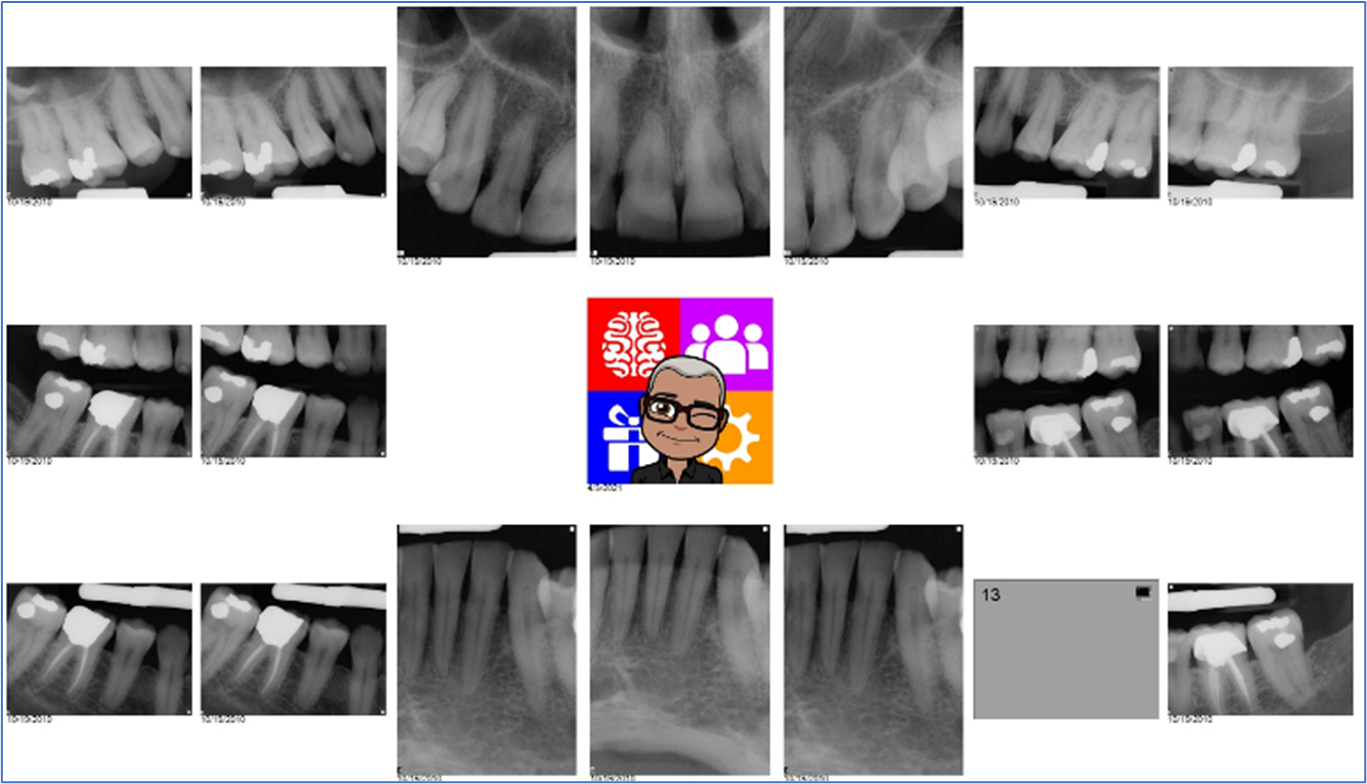

How Andre Exports a FMX as One Image or Import into a mount into Eaglesoft

Many offices chose to send Patient’s FMX to Insurance or another office as one “mounted” image instead of 18 individual images. Here are some options:

Remember that the resolution/image quality will be much lower in an exported single image versus the individual images.